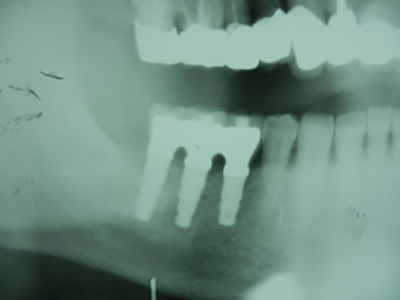

ふくしま歯科医院では、患者様の身体的・経済的負担を最小限に抑えた先進的インプラント治療を提供しています。特に「サージカルガイドを用いた傾斜埋入法」は同院が誇る専門技術です。

従来のインプラント治療では、上あごの骨が薄い場合、人工骨を作る処置が必要でした。この方法は腫れや痛みを伴い、治療費も高額になりがちです。しかし当院の傾斜埋入法では、骨の薄い部分を避けて最適な角度でインプラントを埋入することで、骨造成手術を回避できます。

実際の治療例では、わずか4.53ミリの骨厚でも対応可能です。治療前には精密な検査と入念なシミュレーションを行い、専用のサージカルガイドを作成。これにより正確な位置への埋入が実現し、体への負担を大幅に軽減しています。